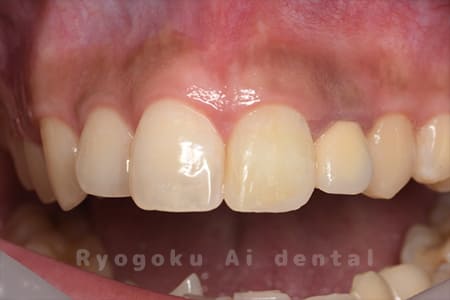

Case03

-

- 原因

- 失活による歯牙変色

- 治療内容

- ブリーチング+マイクロエンド+ダイレクトボンディング

- 治療費用

- 198,000円(ブリーチング55,000円+マイクロエンド77,000円+ダイレクトボンディング66,000円)

前歯が黒いのが気になるとのことでご来院された患者様です。根の状態も悪かったためマイクロスコープ下で根管治療を行い、ブリーチングの後にダイレクトボンディングで形態修正を行いました。

<リスク・副作用>

治療中もしくは治療後に急に痛みが出る場合があります。感染が強い場合には痛みが激しいことがありますので、その際は痛み止め、抗生剤を処方する場合があります。

また、ダイレクトボンディングは強い衝撃などにより欠けたりすることがある。経年的に劣化(変色)してくる可能性がある。